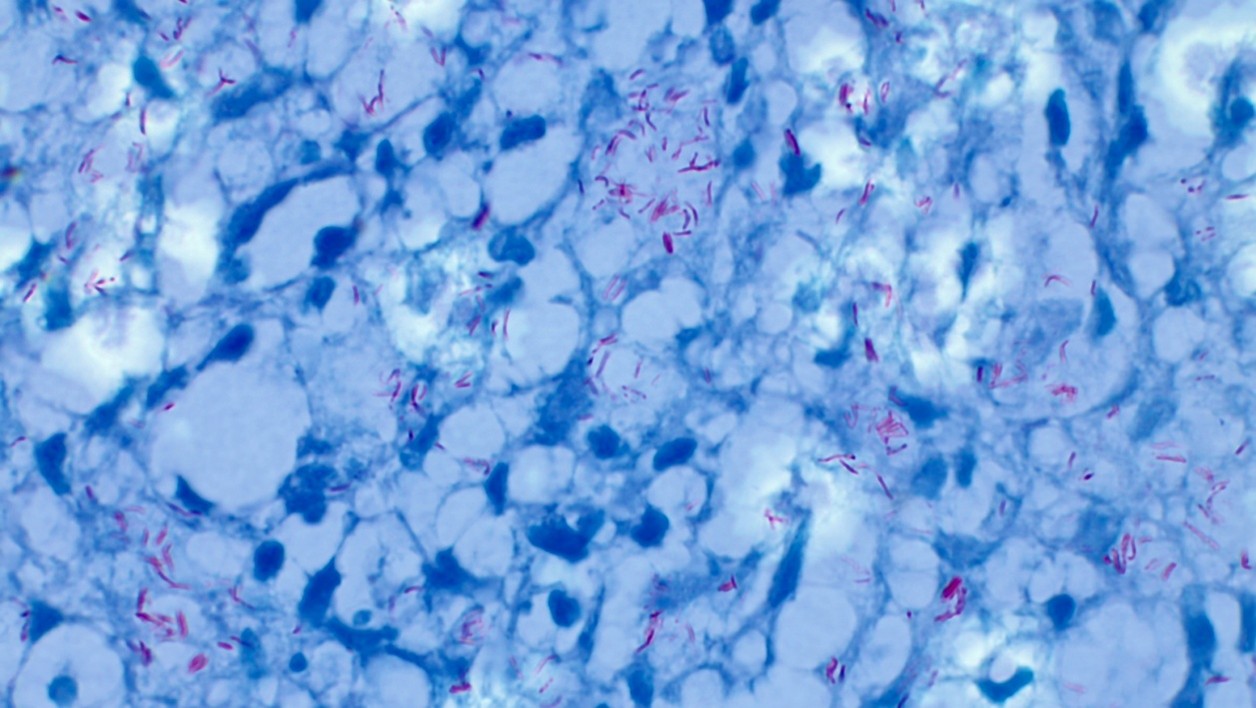

Mycobacterium leprae, in a case of Hansen disease – Lepromatous type

Fig (1): Microphotograph showing lepra bacilli (Mycobacterium leprae) in a case of Hansen disease – Lepromatous type (Fite-Faraco stain, ×1000)

M.leprae is an obligate intracellular organism. M. leprae parasitizes histiocytes (skin macrophages) and Schwann cells in the peripheral nerves. The WHO has designated leprosy as a neglected tropical disease (NTD). The Global Leprosy Strategy for the years 2021–2030 entitled “Towards zero leprosy” has begun. Leprosy has been classified into five types using the Ridley-Jopling classification: tuberculoid (TT), borderline tuberculoid (BT), mid-borderline (BB), borderline lepromatous (BL) and lepromatous (LL). Due to its higher lipid content, M. leprae does not become discoloured by acid-alcohol with the Ziehl-Neelsen stain, a red stain that contains fuchsin. Thus, it appears as characteristic acid-alcohol-resistant bacilli. A large number of bacilli are observed within foamy histiocytes with LL lesions in Fite-Faraco stain. The M. leprae cell wall includes more mycolic acid than that of M. tuberculosis (the ratio of mycolic acid to PGN is 21:10 versus 16:10).2

In lepromatous leprosy, macrophages may be distended with large groups of lepra bacilli (globi); bacteria are present in large numbers in cutaneous nerves and in endothelium and media of small and large vessels.